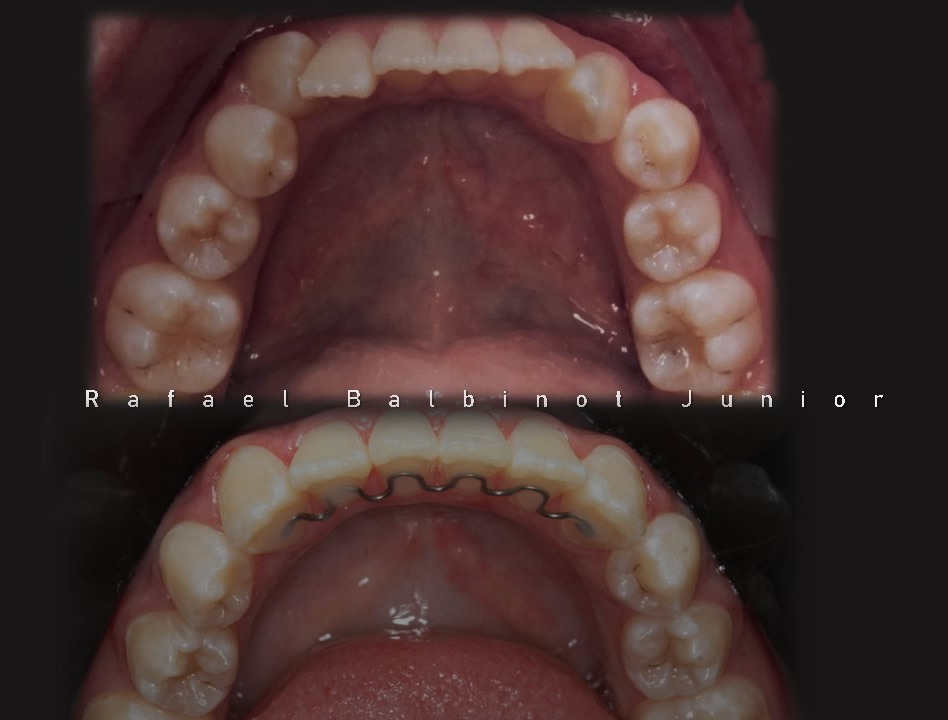

A Ortodontia é a especialidade que trata o mau posicionamento dos dentes e/ou das arcadas dentárias. Dentes tortos e fora da posição correta prejudicam de forma significativa a estética, a harmonia do sorriso e a função mastigatória. Confira os sorrisos transformados pelo Instituto Balbinot.